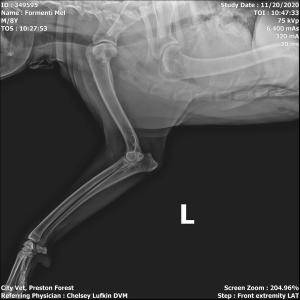

A 9-year-old Catahoula mix presented to the veterinary clinic with a limp in his left front leg.